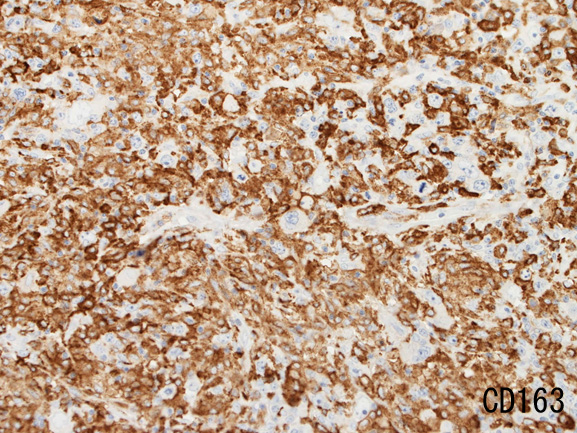

腫瘍細胞はCD20+, CD30+, CD15-, PAX-5+, Oct.2+, BOB.1+(Oct2, BOB1は田丸先生の染色結果), EBER-ISH+, EBNA2-

背景細胞はCD3+ Tリンパ球(CD8>CD4)とCD163, CD68陽性組織球。

| MUM-1 | CD3 | 背景組織球はCD163+ | |